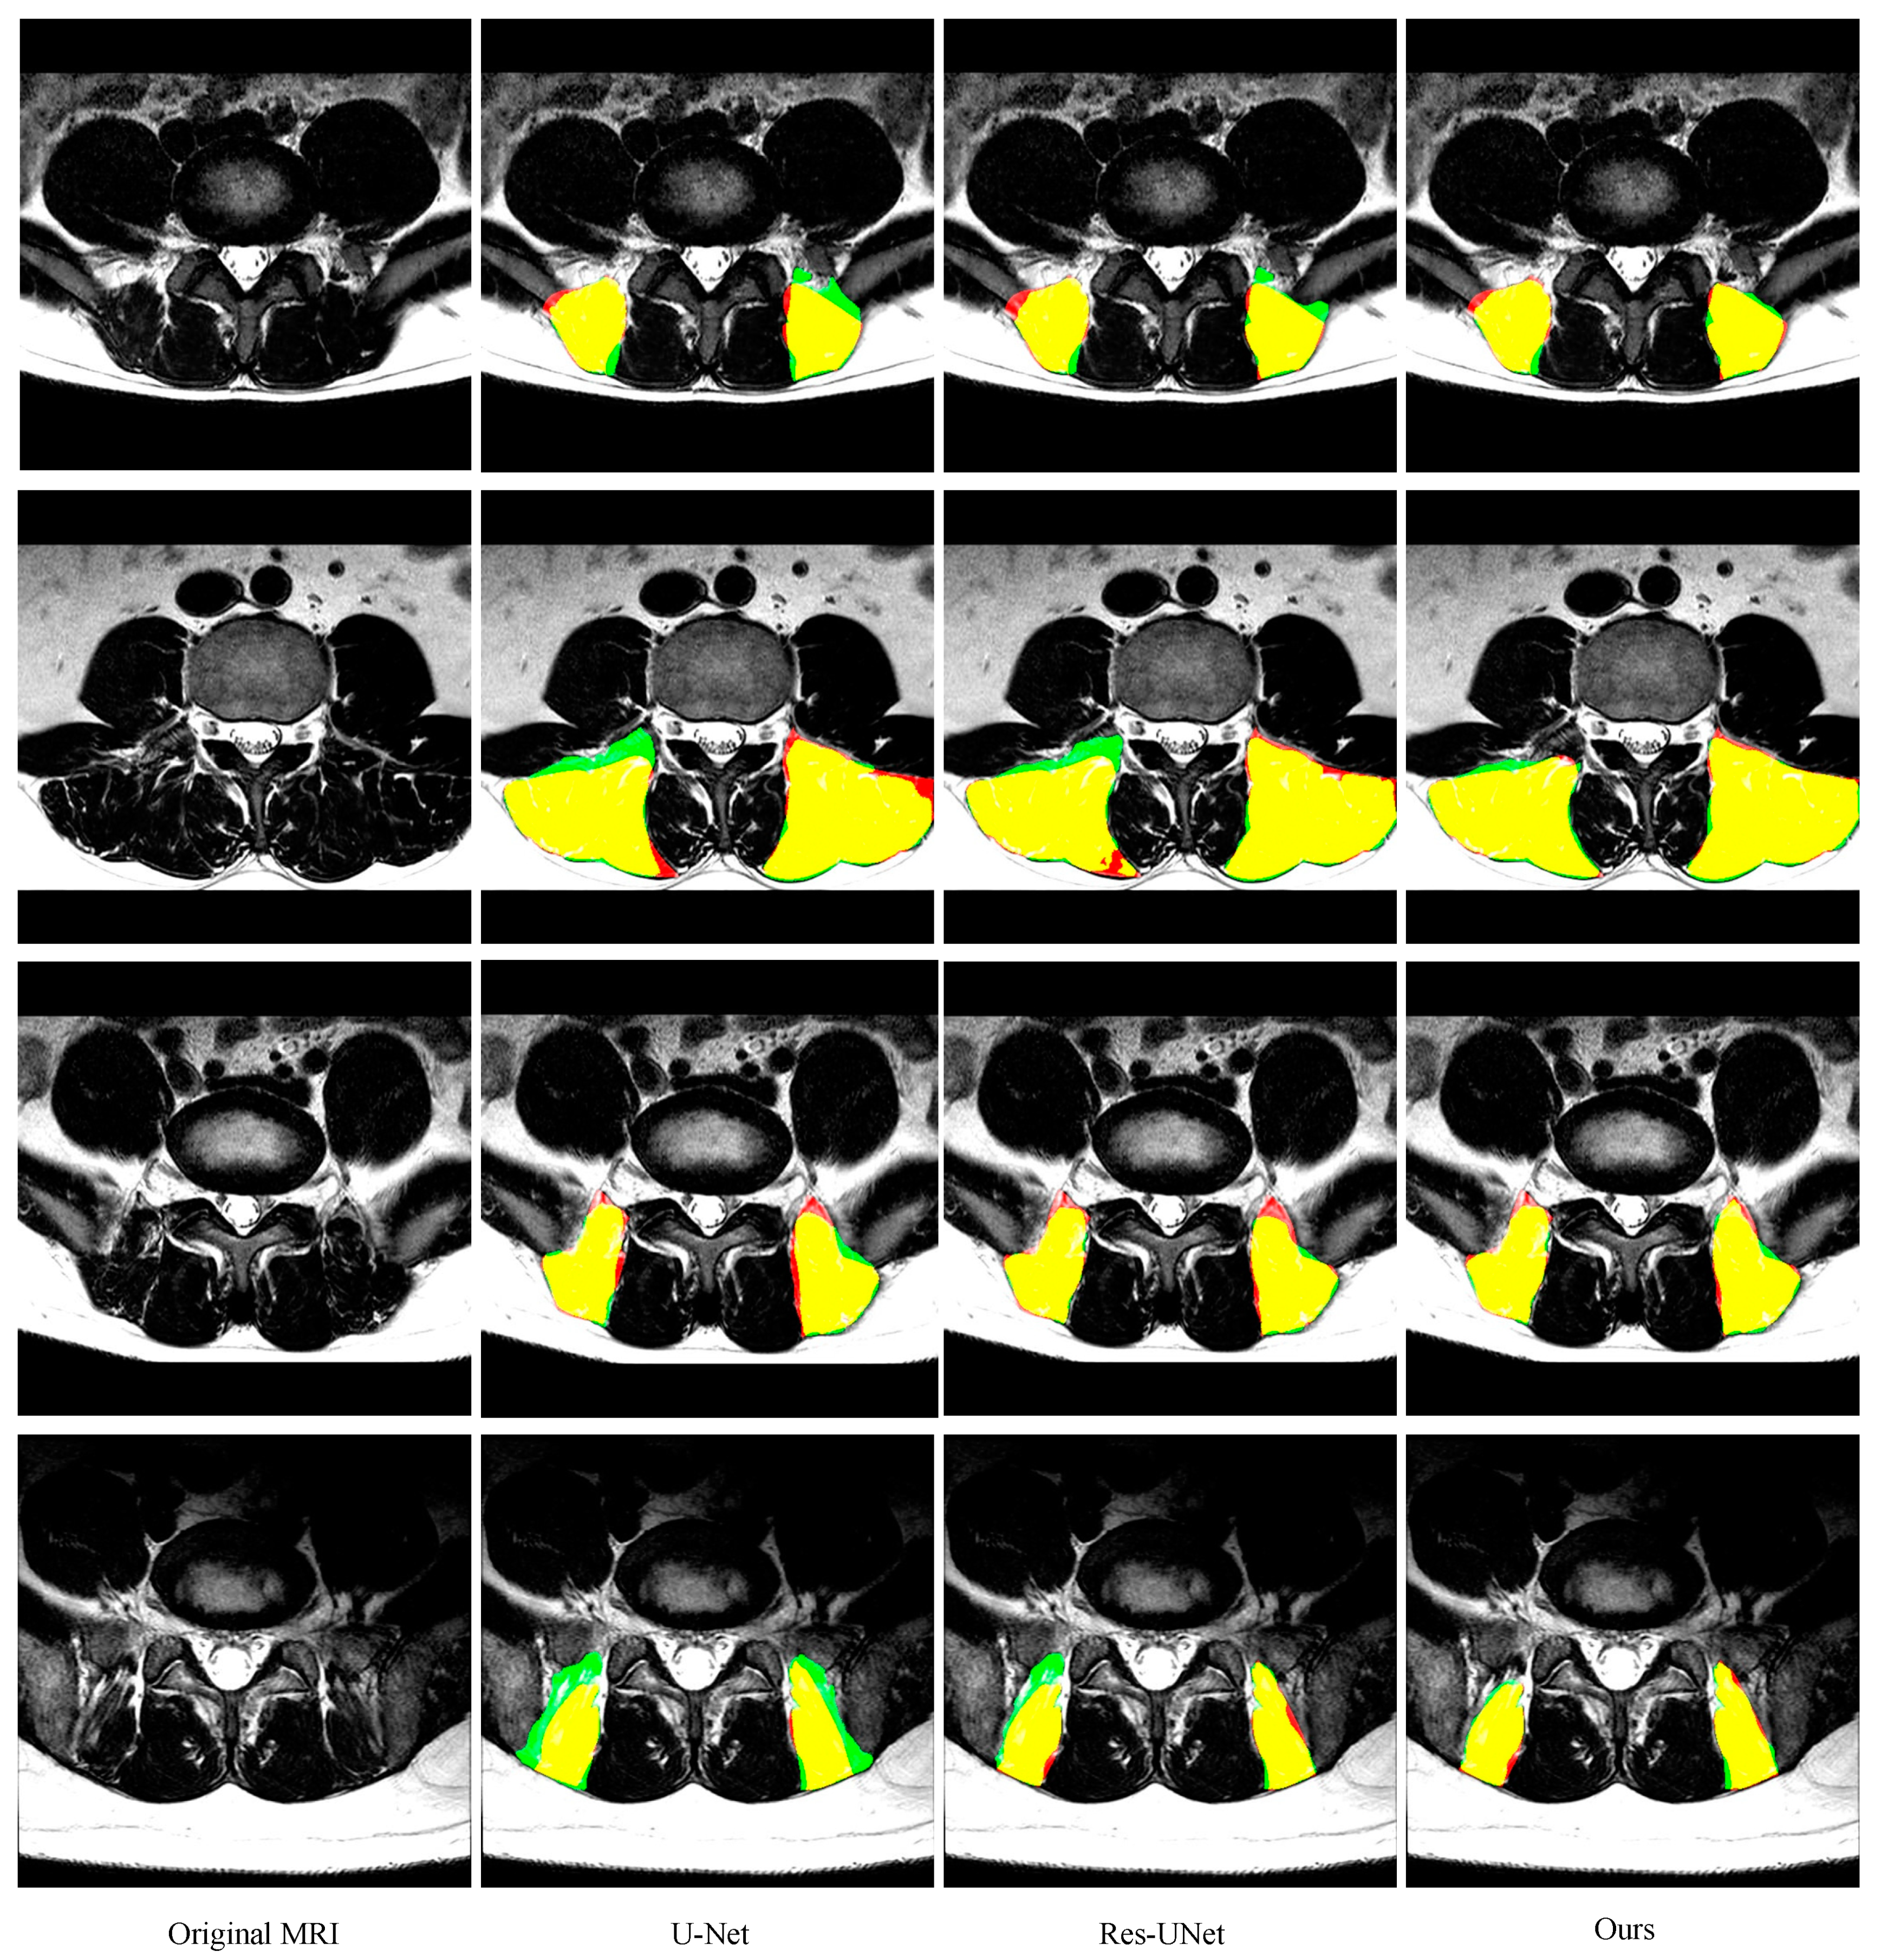

3.5. Comparison with other State-of-the-Art Methods

| FCN | 0.873 ± 0.079 | 0.865 ± 0.075 | 0.892 ± 0.111 | 15.24 ± 14.85 |

| SegNet | 0.904 ± 0.082 | 0.918 ± 0.096 | 0.901 ± 0.092 | 9.9 ± 9.85 |

| PSPNet | 0.901 ± 0.081 | 0.90.1 ±0.089 | 0.915 ± 0.098 | 8.46 ± 6.55 |

| DeepLabv3+ | 0.908 ± 0.077 | 0.919 ± 0.075 | 0.908 ± 0.10 | 8.19 ± 5.92 |

| U-Net | 0.895 ± 0.080 | 0.917 ± 0.086 | 0.887 ± 0.105 | 9.75 ± 8.72 |

| ResU-Net | 0.905 ± 0.092 | 0.915 ± 0.102 | 0.902 ± 0.109 | 8.86 ± 8.42 |

| Ours | 0.913 ± 0.082 | 0.920 ± 0.100 | 0.919 ± 0.073 | 7.89 ± 5.61 |